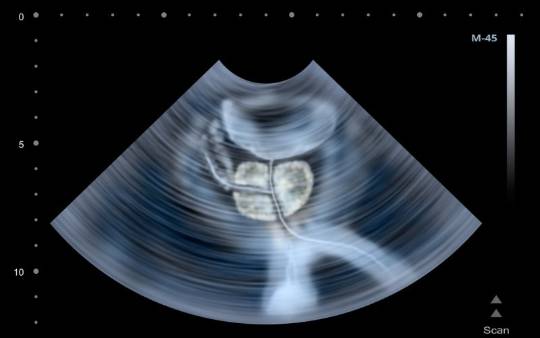

- Ecografía. En algunos casos se recomienda esta prueba con el fin de comprobar cuánto mide la próstata, así como valorar el tracto urinario superior.

- Ecografía transrectal.